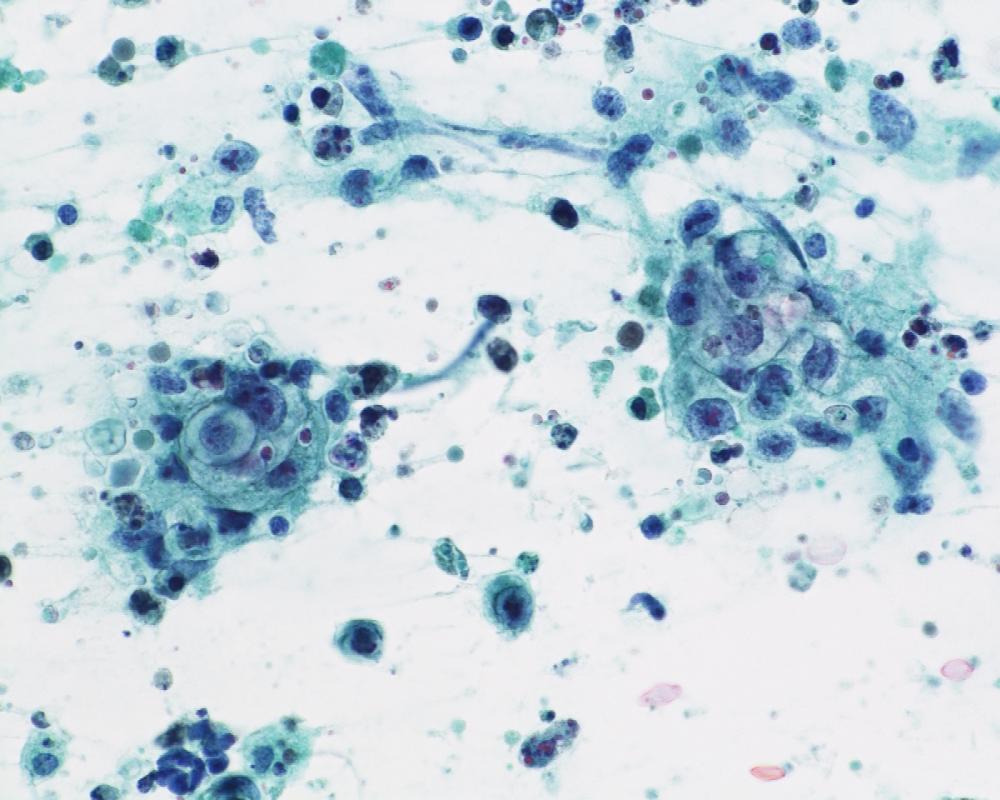

第40回日本臨床細胞学会九州連合会学会(大分)スライドカンファレンス症例3

種別:泌尿器

出題:橋向 圭介 熊本大学病院病理部

| 年齢 | 70代 | 性別 | 男性 |

| 採取部位 | 分腎尿 | 採取方法 | カテーテル |

| 検体処理法 | 2回遠心法(YM式液状検体固定液) |

既往歴:胸椎多発性骨髄腫治療中

現病歴:2021年より胸椎多発性骨髄腫の化学療法中であり、治験前スクリーニングの単純CT検査にて左尿管軟部影を指摘。同時期に腰痛、水腎症が出現し、精査目的のため分腎尿が提出された。

| 正解 | 5.形質細胞腫 |

▼選択肢及び投票結果

| 1.ウイルス感染細胞 | 21件 | (20.0%) | |

| 2.低異型度尿路上皮癌 | 8件 | (7.6%) | |

| 3.高異型度尿路上皮癌 | 30件 | (28.6%) | |

| 4.小細胞癌 | 3件 | (2.9%) | |

| 5.形質細胞腫 | 43件 | (41.0%) | |

| 投票総数 | 105件 | (100%) |